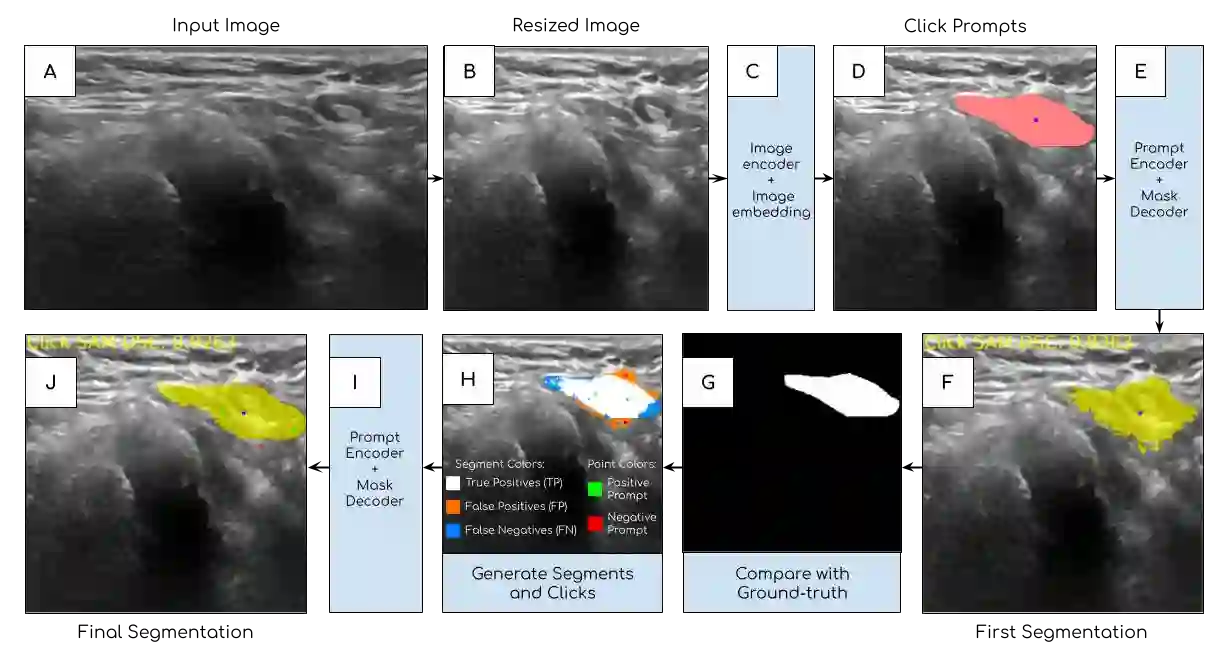

The newly released Segment Anything Model (SAM) is a popular tool used in image processing due to its superior segmentation accuracy, variety of input prompts, training capabilities, and efficient model design. However, its current model is trained on a diverse dataset not tailored to medical images, particularly ultrasound images. Ultrasound images tend to have a lot of noise, making it difficult to segment out important structures. In this project, we developed ClickSAM, which fine-tunes the Segment Anything Model using click prompts for ultrasound images. ClickSAM has two stages of training: the first stage is trained on single-click prompts centered in the ground-truth contours, and the second stage focuses on improving the model performance through additional positive and negative click prompts. By comparing the first stage predictions to the ground-truth masks, true positive, false positive, and false negative segments are calculated. Positive clicks are generated using the true positive and false negative segments, and negative clicks are generated using the false positive segments. The Centroidal Voronoi Tessellation algorithm is then employed to collect positive and negative click prompts in each segment that are used to enhance the model performance during the second stage of training. With click-train methods, ClickSAM exhibits superior performance compared to other existing models for ultrasound image segmentation.